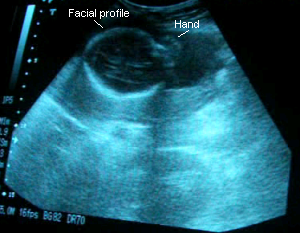

31 Weeks 1 Day

November 28, 2006: Blood pressure and urinalysis were great. Alaethia’s still in the head-down position. I’ve been feeling her little feet in my ribs and tugs around my belly, which the doctor says might be her pulling on the umbilical cord. She’s measuring at 30w3days according to her size although I’m 31 weeks 1 day, which Dr. C. says is fine but it makes me anxious since it might mean she’ll be here later than sooner :P. Although, I would like her to wait till 38 weeks at least! Dr. C. says she’s growing perfectly and confirmed for the 4th time that she’s a girl. From this sono, it looks like she’ll have Eenan’s round face and Jaylen’s lips…and probably my nose. I can’t wait to meet her!

Sono pic:

Alaethia's face.

Just as she was reaching towards her face.